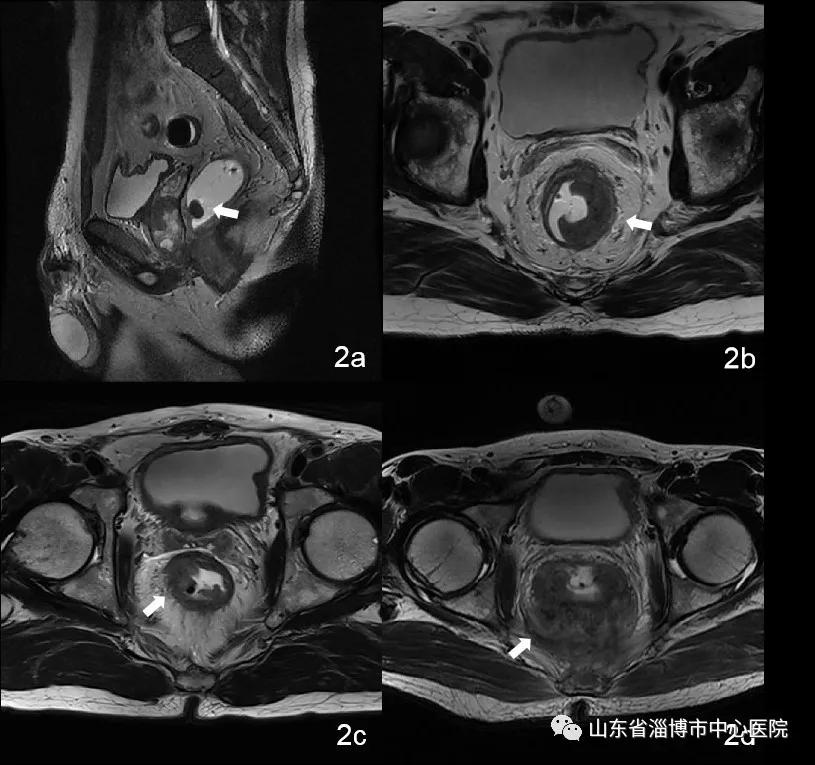

直肠高分辨率MRI图像如下所示。MRI对直肠癌T分期准确率可达80.3%-94.2%,N分期准确率可达70%-90%,为临床治疗方案的选择提供了可靠依据。

图2a:T1期病例,病变较小,侵及粘膜下层,耦合剂灌肠后清晰显示小病变的范围

图2b:T2期病例,病变侵犯肌层未突破肌层

图2c:T3期病例,病变突破肌层到达浆膜层

图2d:T4期病例,病变侵犯直肠周围组织